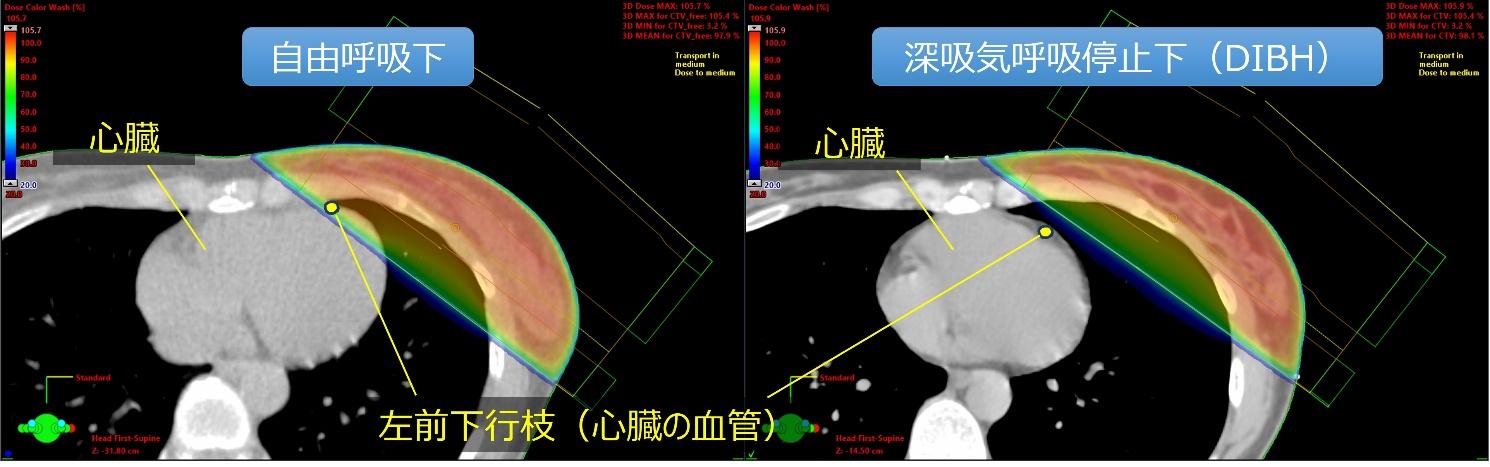

深吸気息止め照射(DIBH)

DIBH(Deep Inspiration Breath Hold)は、放射線治療の際に大きく息を吸い、一定時間呼吸を止めた状態で照射を行う方法です。特に左乳房照射などで用いられ、深く吸気することで肺が膨らみ、心臓が胸壁から離れるため、心臓への放射線量を低減できるという原理に基づいています。

ExacTrac Dynamic では、可動式の天吊り室内モニターを用いた患者フィードバックシステムにより、息止めの目標レベルをガイド付きナビゲーションで分かりやすく表示することができ、患者さんが適切な呼吸停止を維持できるよう支援します。